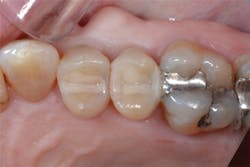

Figure 13: View of teeth Nos. 4 and 5 after curing the final occlusal layer of TPH Spectra composite.

Figure 14: Final restorations on teeth Nos. 4 and 5.